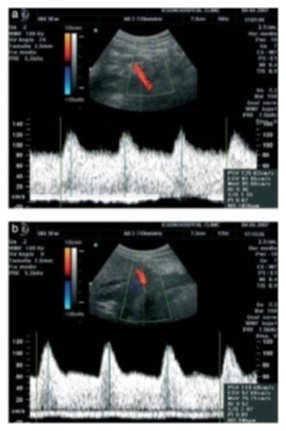

делают доплер при беременности